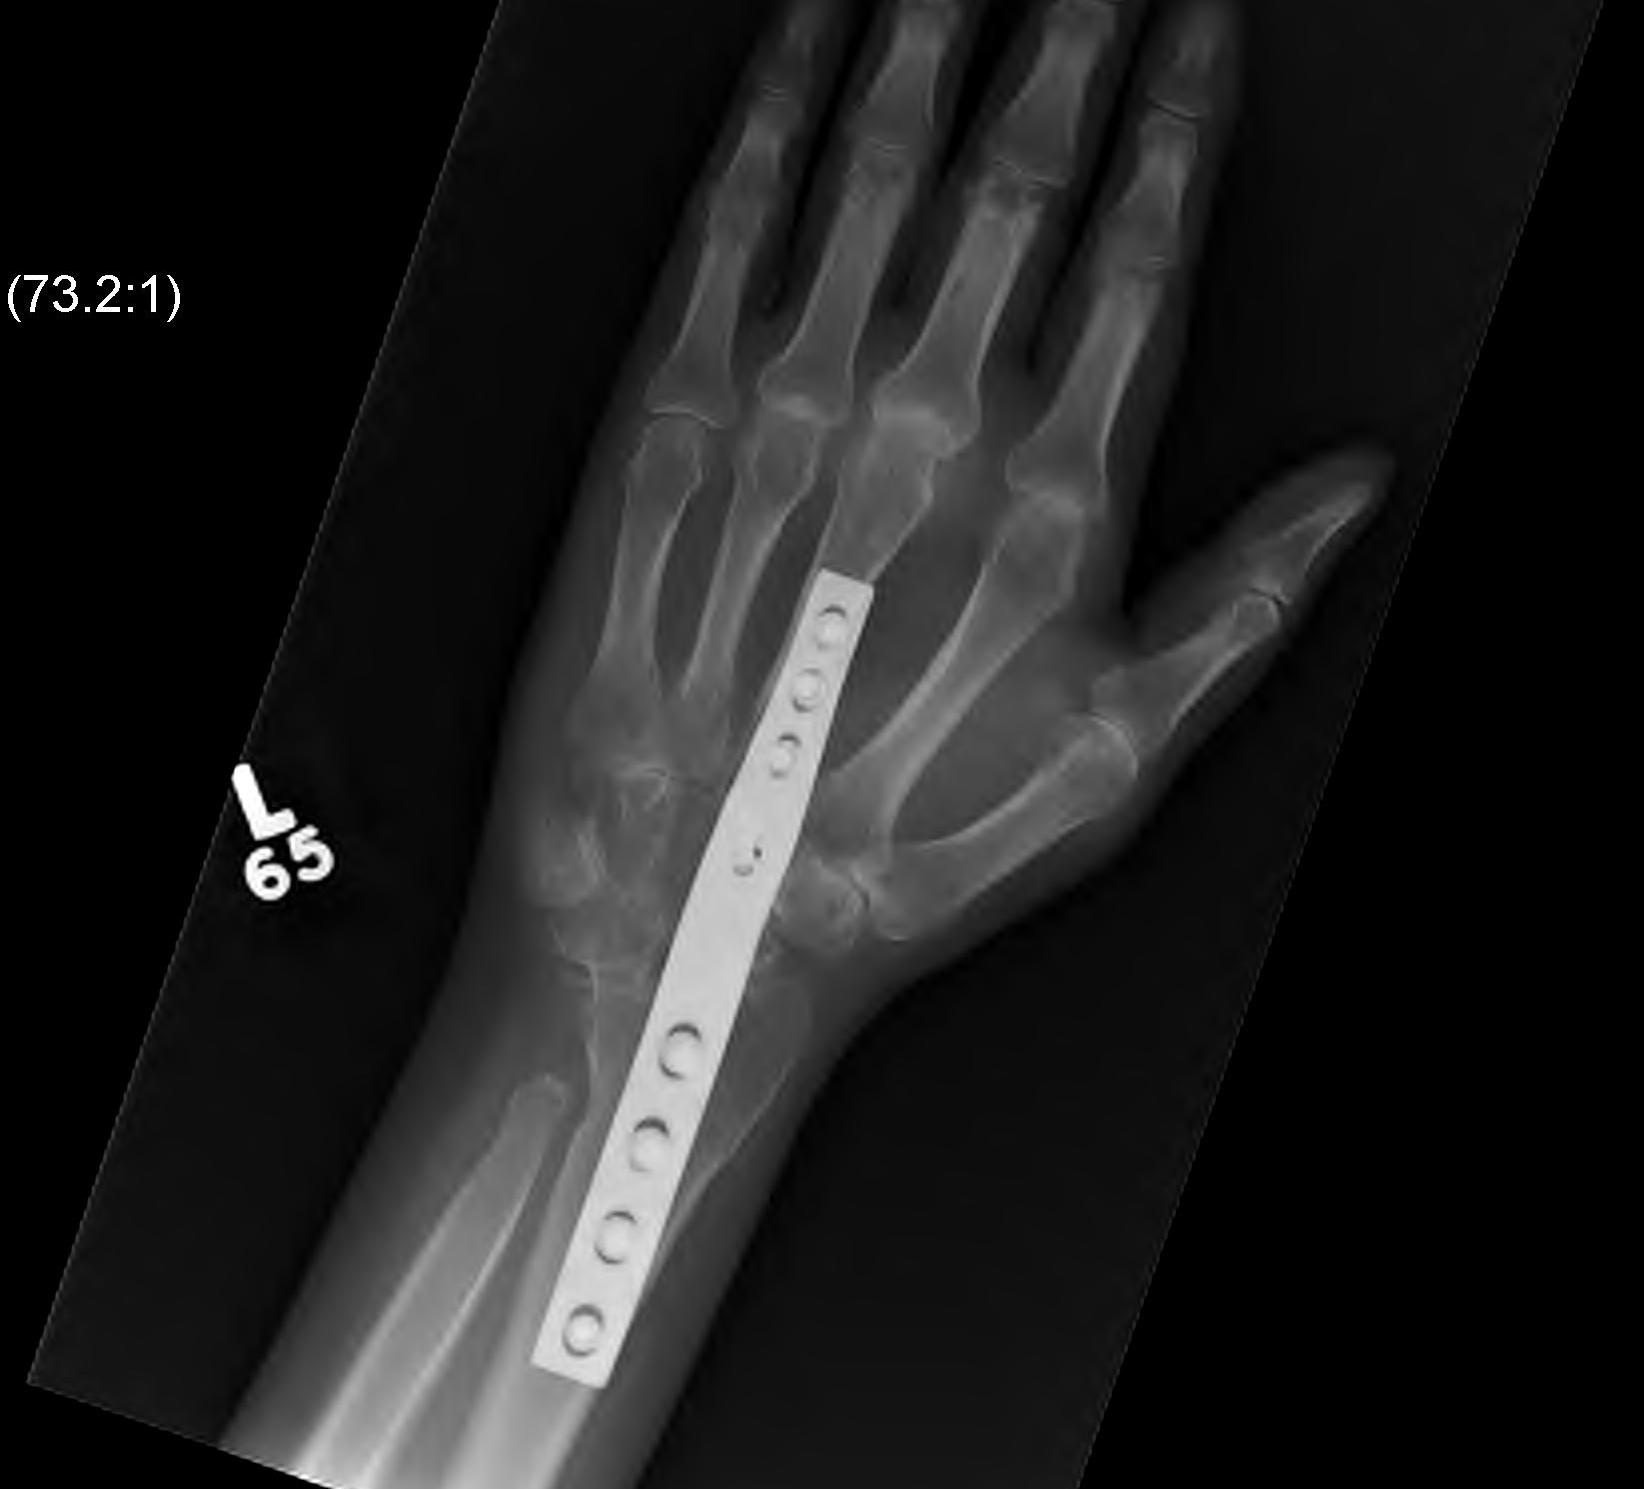

Xray

Wrist arthrodesis

Total wrist arthrodesis